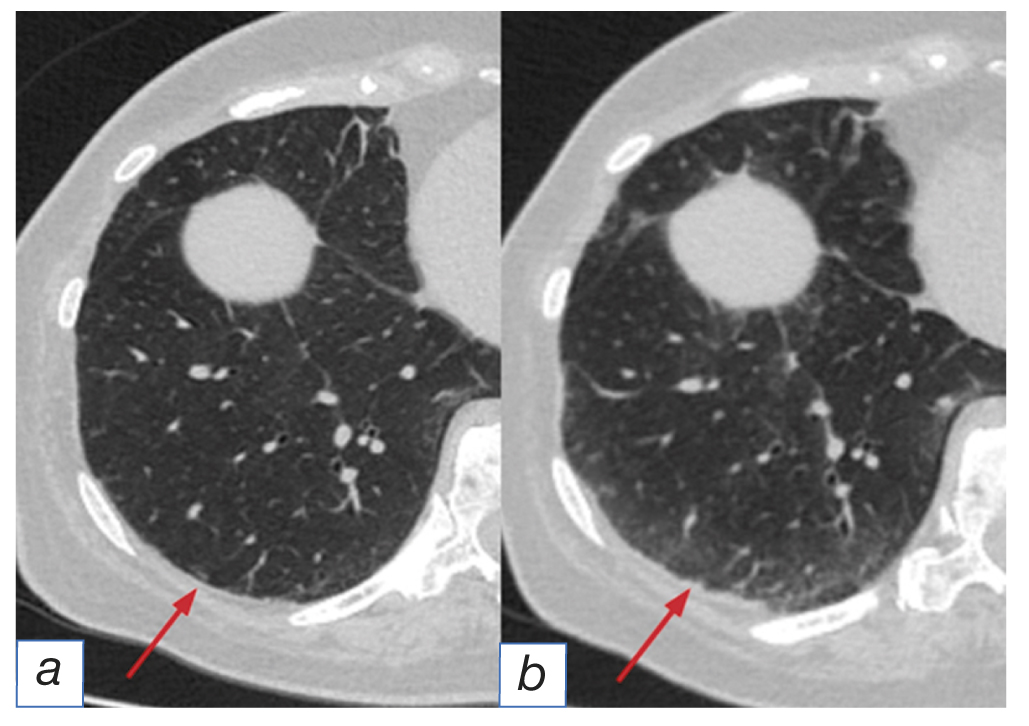

- the pattern of acute respiratory distress-syndrome [10] visualized as diffuse or multifocal increase in the density of pulmonary tissue (ground glass-type) and consolidation, predominantly with anterior-posterior gradient distribution, as well as decreased lung capacity, dilation of bronchi and traction bronchiectases (Fig. 4).

Fig. 4. The pattern of acute respiratory distress-syndrome: before (а) and after (b) immunotherapy (arrows).